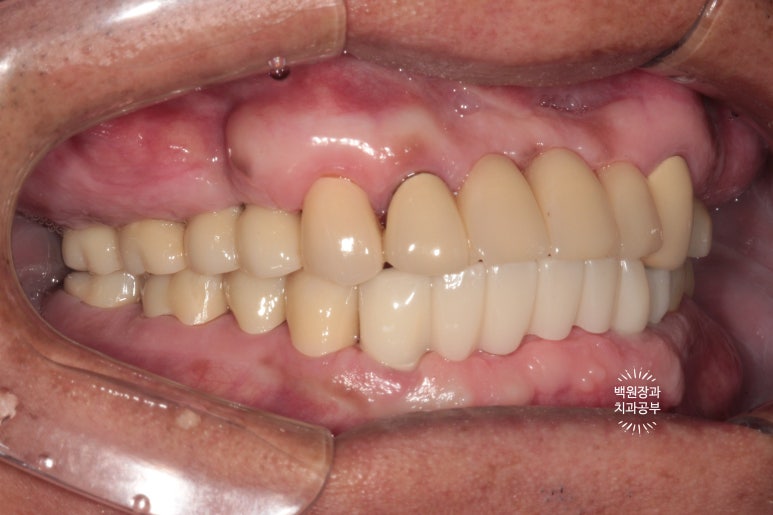

위 어금니와 아래 앞니가 없는 상태입니다.

보시면 아주 최소한의 치아만 닿고 있는게 보이시죠?

성인 남성의 턱 힘을 견뎌내기에 무리가 있어요. 그래서 치아가 자꾸 깨져나가게 되지요.

임플란트라는 것이 있어서, 틀니 없이 회복할 수 있음에 늘 감사하면서 진료하고 있습니다.

여담입니다만, 왼쪽 사진을 보시면 임플란트 상부가 구강내로 노출된 것을 보실 수 있을거에요.

흡연자의 경우 담배 연기가 혈관이 수축하게 하는 역할을 하기 때문에 치유가 상당히 더뎌집니다.

그래서 수술 부위가 불완전하게 아물게 되고, 원치 않게 임플란트의 일부가 노출되게 되어요.

또한 골재생도 불량해지고 이후 임플란트의 예후 또한 좋지 않습니다.

그래서 이러한 치료를 받으시기 전에 금연이 선행되어야 하는 것이 원칙입니다.!!

시간이 흘러 잇몸이 아물고 위 임플란트의 임시 보철물을 제작해 드렸습니다.

왼쪽은 임플란트에 맞춤형 지대주 (custom abutment)를 연결한 사진이고,

오른쪽은 그 맞춤형 지대주에 임시치아 (temporary crown)을 접착한 사진입니다.

왜 임시 치아를 만드냐구요?

이렇게 오랜만에 어금니가 생기는 경우, 환자분이 쉽게 적응하여 씹는 기능을 발휘하시기 쉽지 않아요.

저는 재활치료라는 표현을 쓰는데요, 마치 재활치료를 하듯 새로 생긴 임플란트를 사용하는 연습시간을 갖는것이지요. 보통 빠르면 2주, 느리면 4주 정도 걸렸던 것 같아요.

같은 방법으로 아래 앞니에 맞춤형 지대주와 임시치아를 제작하여 접착해드렸어요.